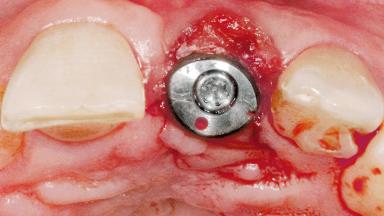

Late Flapless Placement of an Implant in a Maxillary Left Central Incisor Site

A 39-year-old male patient presented with a chief complaint of discomfort and gingival discoloration around his maxillary left central incisor. He was in good general health and was a non-smoker. His past dental history was significant because of the traumatic fracture of tooth 21 in a sporting accident at age 13. Initial dental treatment included endodontic therapy and a full-coverage restoration. The patient became symptomatic 5 years later, when structural failure of the tooth resulted in the dislodgment of the crown. Endodontic retreatment, apical surgery, and post-and-core restoration were performed.

Bone Augmentation Horizontal|Staged

Augmentation Materials Xenogenous|Membrane

Soft Tissue Grafting Simultaneous